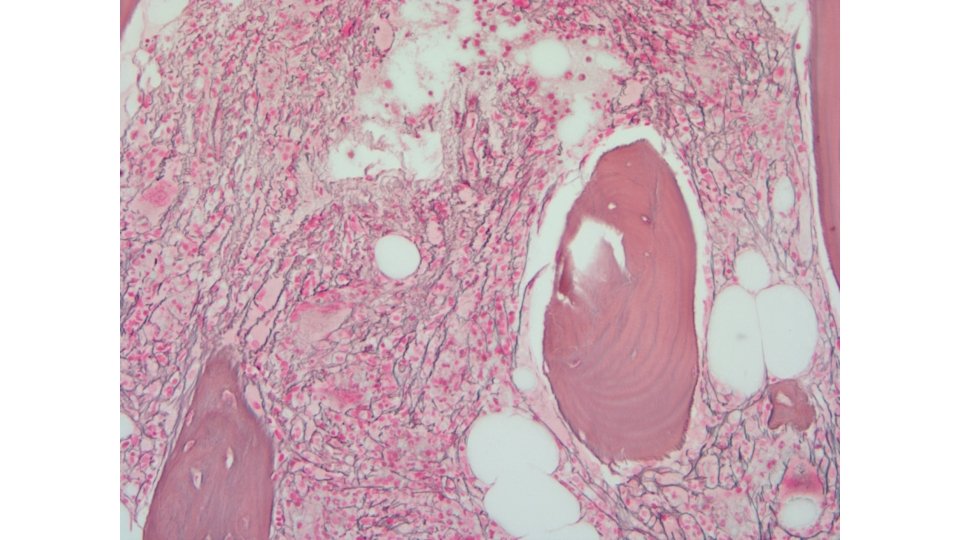

Overview of Myelofibrosis (MF) Ph positive BCR-ABL Myeloproliferative Neoplasms 1 Ph negative CML PV Primary MF Post-PV MF ET Post-ET MF MYELOFIBROSIS MF prevalence • Approximately 16, 000 to 18, 500 patients in the United States 2 MF is characterized by • Bone marrow fibrosis, cytopenias, and constitutional symptoms 3 • Splenomegaly 4 MF, myelofibrosis PV, polycythemia vera ET, essential thrombocythemia CML, chronic myeloid leukemia 1 Tefferi 4 Mesa MF natural history • Time course of disease progression is highly variable but frequently characterized by a period of stable disease followed by a late stage with rapid clinical progression 5, 6 A, Vardiman JW. Leukemia. 2008; 22: 14 -22; 2 Data on file, Incyte Corporation; 3 Verstovsek S. Clin Can Res. 2010; 16: 1988 -1996; RA. Blood. 2009; 113(22): 5394 -5400; 5 Cervantes F, et al. Blood. 2009; 113: 2895 -2901; 6 Tam CS, et al. J Clin Oncol. 2009; 27: 5587 -5593.

Myelofibrosis: Clinical Manifestations 1 Constitutional symptoms Fatigue, weight loss, cachexia, pruritus, night sweats, bone/joint pain, low-grade fever, cough Marked hepatosplenomegaly Early satiety, abdominal discomfort, painful splenic infarcts, portal hypertension, cachexia Nonhepatosplenic extramedullary hematopoiesis (rare) Cord compression, ascites, pulmonary hypertension, pulmonary embolism, lymphadenopathy, skin tumors Thrombohemorrhagic complications Marked leukocytosis or thrombocytosis; severe anemia, thrombocytopenia, neutropenia; hyperuricemia Splenomegaly 2 Increased risk of leukemic transformation 1. Barbui T et al. J Clin Oncol. 2011; 29: 761 -770. 2. Image provided courtesy of S. Verstovsek.